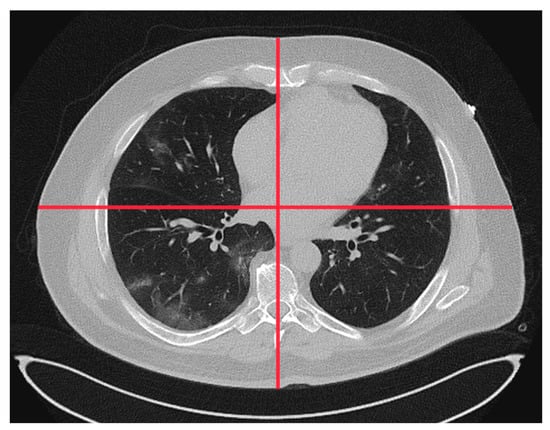

4.2. Image Quality